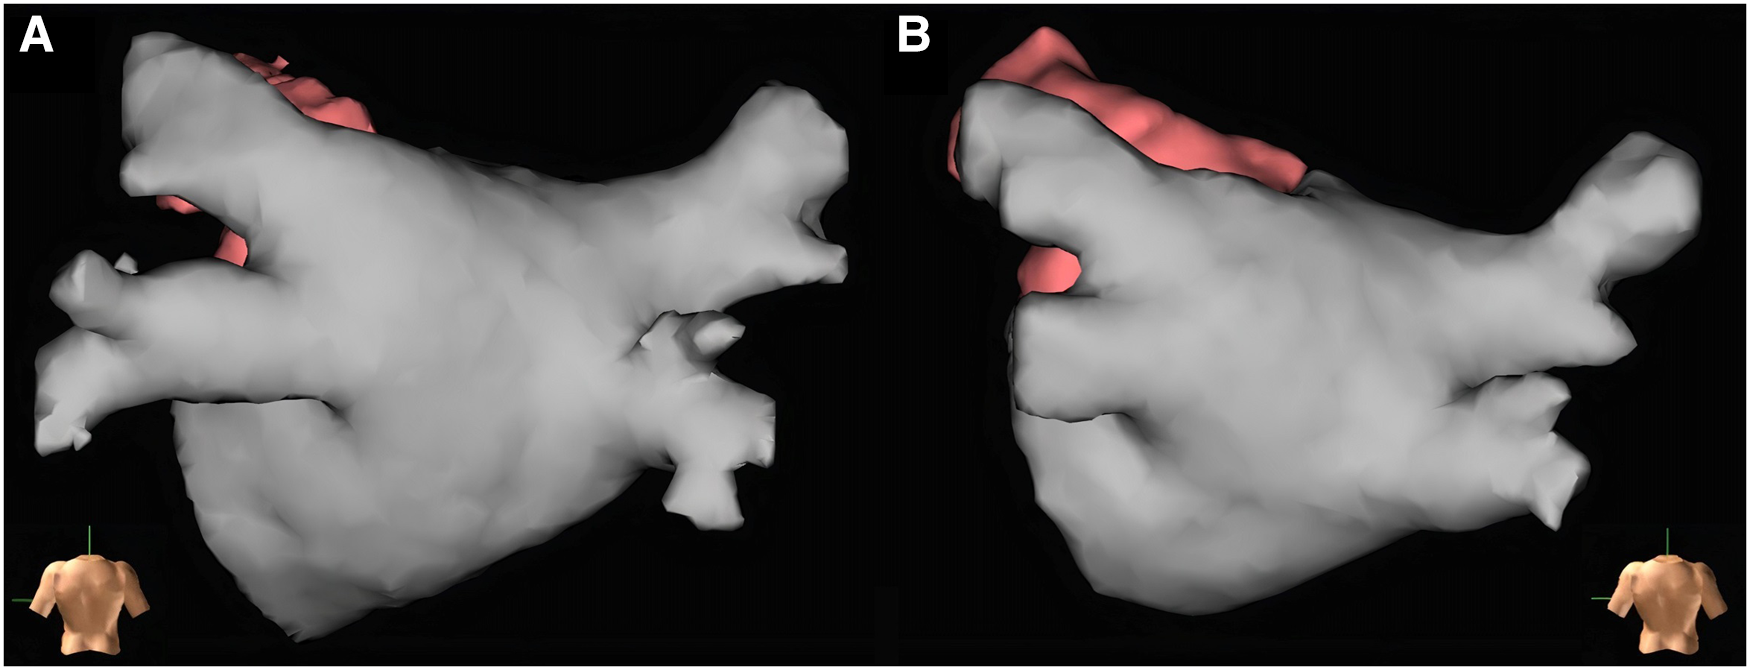

3.5. Electrophysiologists' evaluation of the usefulness of LA contrast-enhanced CT vs. CMR regarding RFCA planning

Twenty-five patients had both LA contrast-enhanced CT and CMR before the ablation procedure. Based on the operating electrophysiologists' subjective opinion (1–10 scale), the quality of the LA contrast-enhanced CT scans was better compared with the image quality of the non-contrast-enhanced CMR BOOST sequence [8 (7–9) vs. 6 (5–7), p < 0.0001] (Figures 3A, B). Still, they found the CMR images appropriate for procedural planning in 43 out of 47 cases (91%).

Figure 3

Left atrial reconstructions before radiofrequency catheter ablation for procedural planning based on left atrial contrast-enhanced CT and CMR BOOST bright-blood images created with EnSite Precision electroanatomical mapping system. Both reconstructions show the left atrium of the same patient (Heart and Vascular Center, Semmelweis University). Panel (A): Reconstruction based on left atrial contrast-enhanced CT images. Panel (B): Reconstruction based on left atrial CMR BOOST bright-blood images.

In addition to ruling out LAA thrombus, imaging prior to RFCA has an essential role in procedural planning by assessing LA anatomy. Certain atrial and PV variations have been shown to influence the recurrence of AF after ablation (23, 24, 33–35). In addition, PV variations may also influence the choice of ablation tools (e.g., the feasibility of cryoballoon ablation, 31- or 35-mm device for FARAPULSE pulsed field ablation) and ablation outcomes. Thus, pre-procedural imaging to assess LA anatomy before AF ablation is common practice (13, 36, 37). Currently, the standard imaging examination used for AF ablation planning at our clinic is contrast-enhanced LA CT. We interviewed cardiac electrophysiologists at our clinic who used both contrast-enhanced LA CT and non-contrast-enhanced CMR BOOST sequences for pre-ablation imaging. They reported that, although image quality was inferior to contrast-enhanced CT, the CMR BOOST sequence imaging still provided adequate information on LA and PV anatomy for ablation planning (Figures 3A, B). The reliability of BOOST in RFCA planning and measurements is also supported by the fact that no significant difference was found in PV ostial area assessment compared with contrast-enhanced CT (all p > 0.05) (Table 5). Thus, in the future, the BOOST sequence may be an alternative to TEE for excluding LAA thrombi and might also replace contrast-enhanced CT for determining LA anatomy before catheter ablation. This might be especially true in young patients with a greater concern regarding ionizing radiation and in cases of impaired renal function.